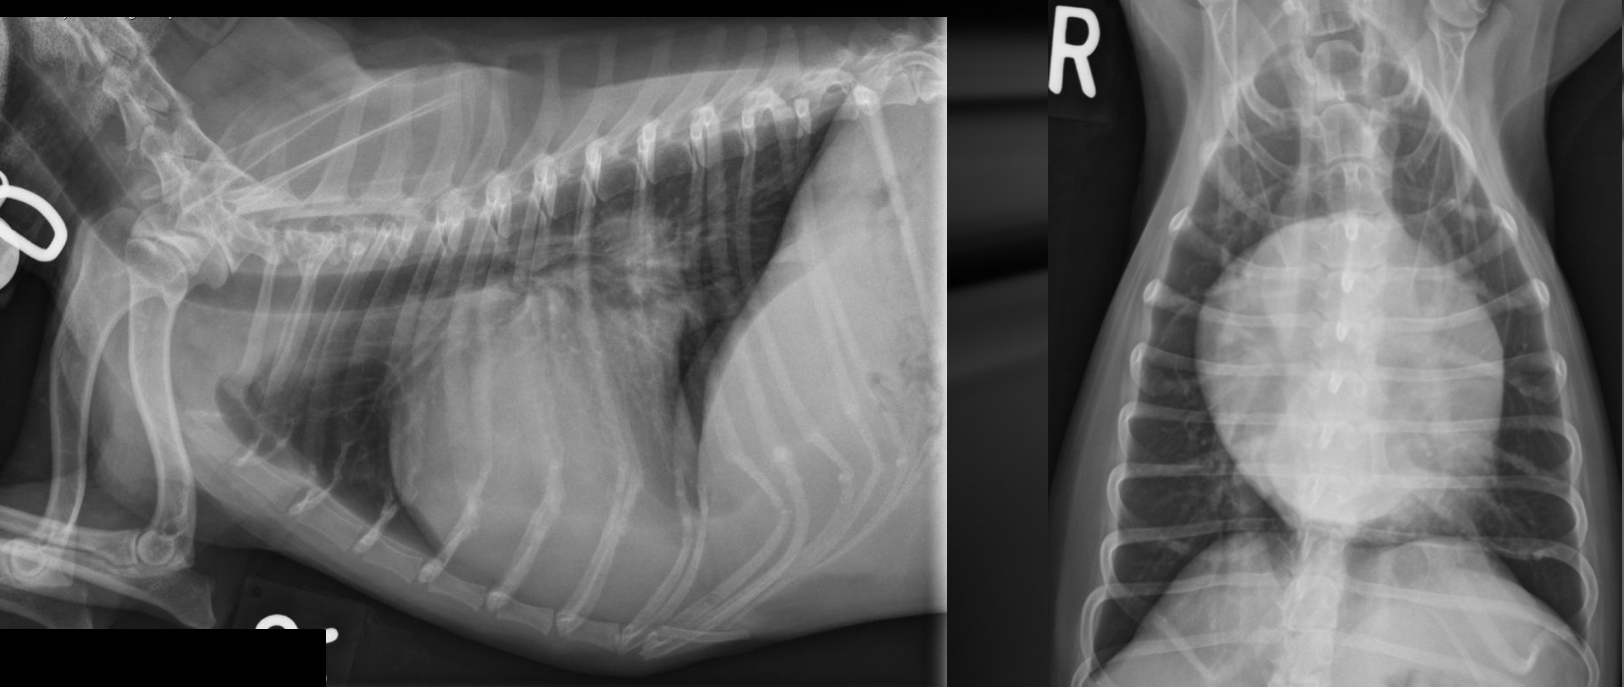

Generalized cardiomegaly in cats features and what disease associated with this

-change in shape = abnormal (hard to tell what chamber affected tho) —> results in valentine shape

-HCM —> big LA and L. Au —> probably baggy left atrium that makes the whole thing look “huge”

What part of the heart is enlarged in this cat

Generalized (the whole thing)